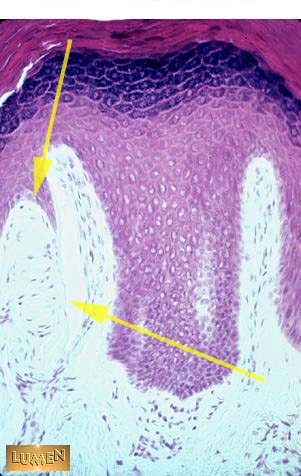

What type of sensory information does this structure pick up?

Light touch